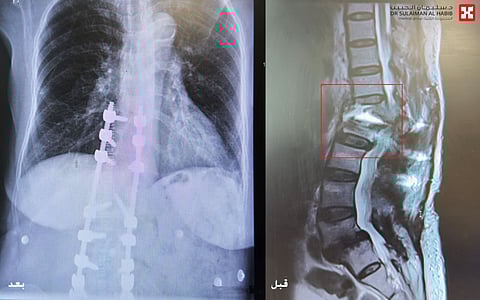

والذي أضاف بأن المراجعة حضرت للعيادة على كرسي متحرك، حيث تم الإستماع إلى شكواها والإطلاع على ملفها الطبي وإجراء الفحص السريري، وتبين أنها فقدت القدرة على الوقوف والمشي منذ شهر، وذلك بعد خضوعها لخمس عمليات سابقة في العمود الفقري، موضحاً أن فحوصات الرنين المغناطيسي (M.R.I) والتصوير المقطعي (C.T. Scan) والأشعة السينية الرقمية (Digital X-Rays) والتحاليل المخبرية، أثبتت إصابتها بكسر وإنفصال الفقرة الأولى القطنية عن العمود الفقري، وحدوث ضغط شديد على الحبل الشوكي والأعصاب، كما تبين من التحاليل وجود هشاشة عظام من الدرجة المتقدمة.

وقال الدكتور الحبيب أنه بعد دراسة الفريق الطبي لكامل معطيات النتائج، إتخذوا القرار بالتدخل الجراحي العاجل للحيلولة دون إصابتها بمزيد من المضاعفات. موضحاً أنه تم إخضاعها لكشوفات طبية مع أطباء القلب والباطنية والتخدير قبل العملية، وقد اجازوا اجراء العملية. مشيراً إلى أن العملية استغرقت 4 ساعات متواصلة تحت التخدير العام، وتم فيها استخدام تقنيات المجهر الجراحي والملاحة العصبية وأجهزة مراقبة الأعصاب، حيث تم فتح الظهر وإزالة كامل التثبيتات السابقة والمسامير الغير مستقرة، تبع ذلك معالجة تشوه العمود الفقري حول الكسر بالفقرة القطنية الأولى، واستخدام مسامير خاصة متوافقة مع مرضى هشاشة العظام تتميز بقدرة تثبيت عالية. نقلت بعدها المراجعة للعناية المركزة لمدة 24 ساعة،ومن لجناح التنويم وخلال 24 ساعة تحسنت مؤشراتها الحيوية ولله الحمد، وقد استطاعت المشي بمساعدة أخصائي العلاج الطبيعي وخرجت من المستشفى بعد 48 ساعة. مؤكداً على أن المريضة عادت لزيارة العيادة بعد أسبوعين وهي بصحة جيدة بعد أن تمكنت من المشي، وعادت لممارسة حياتها الطبيعية.